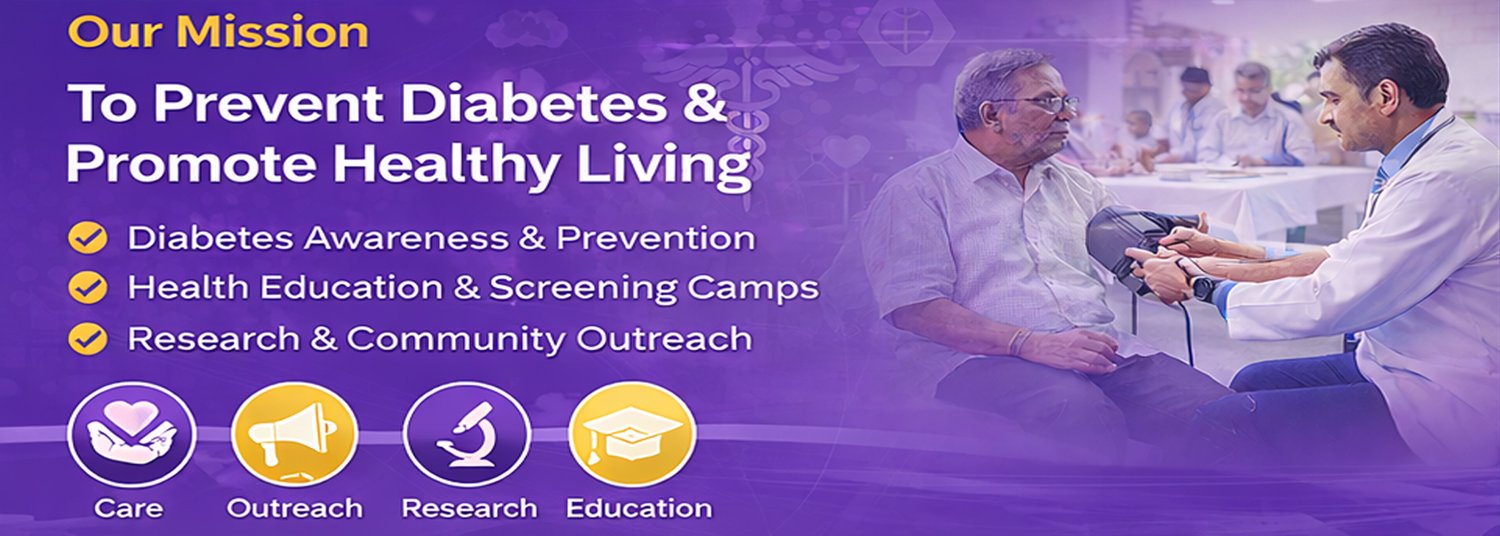

DiaWell C.O.R.E. Foundation is a company incorporated under Section 8 of the Companies Act, 2013, established with charitable and not-for-profit objectives. The Foundation has been formed with a clear commitment to improving healthcare outcomes, particularly in the prevention, control, and management of diabetes and other lifestyle-related diseases.

With the growing prevalence of diabetes and non-communicable diseases in India, there is an urgent need for structured awareness, early detection, community education, and accessible healthcare support. DiaWell C.O.R.E. Foundation aims to bridge this gap through comprehensive health initiatives, research-driven approaches, and collaborative partnerships.

Care

Providing counselling, screening services, and support systems for individuals at risk of or living with diabetes and related conditions. We focus on early detection, patient guidance, and long-term disease management strategies.

Outreach

Conducting community-based health awareness campaigns, rural health initiatives, screening camps, and public engagement programs to reach underserved and vulnerable populations.

Research

Undertaking and supporting research initiatives aimed at understanding disease patterns, preventive strategies, and innovative healthcare delivery models. We encourage evidence based solutions to improve public health outcomes.

Education

Organizing workshops, seminars, training programs, and awareness sessions for patients, caregivers, healthcare workers, and institutions to strengthen capacity and knowledge in diabetes management and prevention.